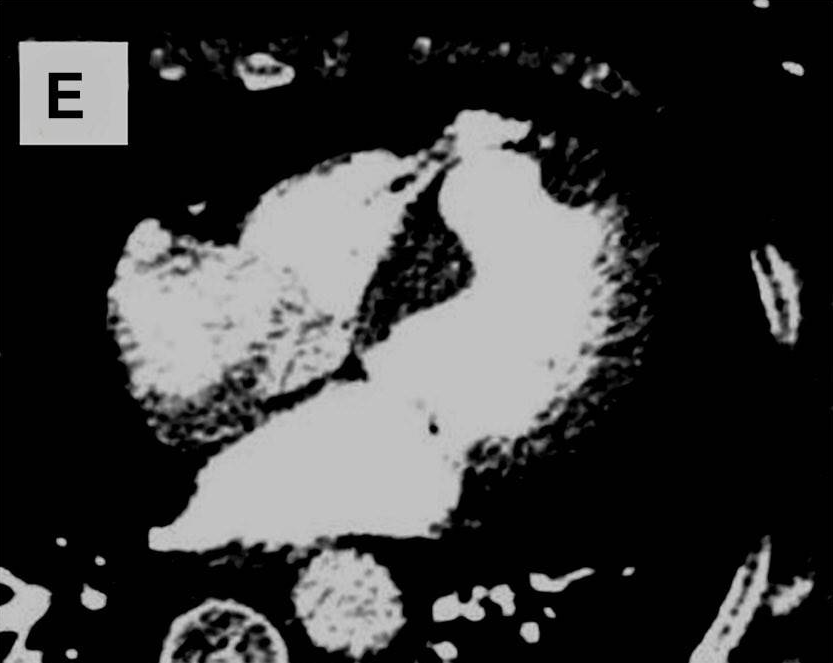

患者女性,69岁,因体检心电图发现T波改变,到心脏科就诊。患者既往无心脏相关病史及心血管危险因素。超声心动图检查发现室间隔肌部瘤样膨出,未发现左向右分流。冠状动脉造影证实冠状动脉正常。左心室造影可见室间隔肌部瘤形成。进一步行心脏CTA及MRI检查,结果显示巨大室间隔肌部瘤,直径与胸主动脉直径相当,未见血栓形成。鉴于患者无症状且无血流动力学影响,采取保守治疗策略,包括生活方式干预、定期心脏监测及规律随访。虽考虑预防性抗凝治疗可能会获益,但由于无血栓形成、血流动力学稳定且缺乏其他危险因素,最终未予实施。不抗凝虽可能增加血栓形成风险,但瘤体内的血流状态可能减少了血栓形成机会,避免了抗栓治疗相关的出血风险。嘱患者每6个月复查超声心动图,必要时行MRI检查。随访期间患者持续无症状且无新发异常,故继续维持原监测方案。

图为心电图、冠状动脉造影、经胸超声心动图、CTA及MRI检查结果。心电图显示v2-4导联T波改变(图A)。左心室造影可见室间隔肌部瘤(图C)。超声心动图显示室间隔瘤样结构(图D)。CTA与MRI均显示巨大室间隔肌部瘤(图E、F)。